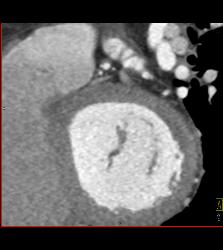

CCTA: Left Anterior Descending Coronary Artery (LAD) Plaque Without Critical Stenosis